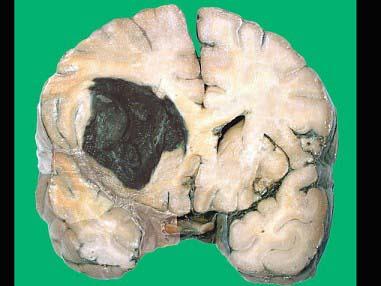

问题 如图为脑出血的大体观,有关该病变的叙述正确的是 ( )

选项 A.通常出血量小 B.属漏出性出血 C.多由于较大的血管破裂所致 D.由毛细血管和毛细血管后静脉通透性增加所致 E.凝血因子缺乏亦是主要原因

答案 C